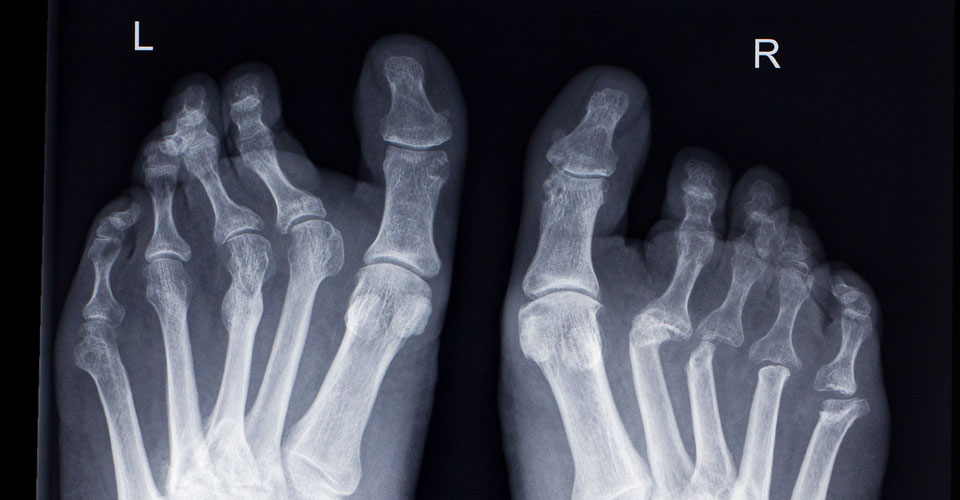

RA usually affects the smaller joints of the hands and feet, but can also affect larger joints such as the hips and knees. As well as the musculoskeletal system, RA can affect body systems and organs such as the lungs, heart, and eyes. Organ changes are most often the result of vasculitis and manifest as ischaemic changes.

Below you will see a range of joint erosion examples.

- Symptoms predominantly presenting in the small joints in hands and feet, plus or minus larger joints.

- Signs predominantly presenting in small joints in hands and feet plus or minus larger joints.

- Joint degeneration - joint erosion may only be identifiable on MRI or CT.